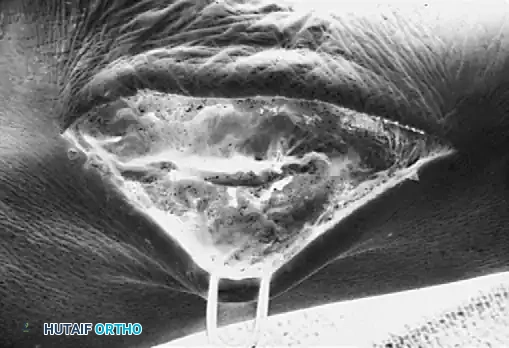

Radiographic Imaging

The 45-degree lateral oblique radiograph is the gold standard for diagnosing a calcaneonavicular coalition. The abnormal bar extends from the anterior process of the calcaneus (just lateral to the anterior facet) dorsally and medially to the lateral/dorsolateral extra-articular surface of the navicular. It typically measures 1 to 2 cm in length and 1 to 1.2 cm in width.

In incomplete coalitions, the adjacent bony margins appear irregular, sclerotic, and indistinct. The talar head may also appear small and underdeveloped.

Advanced Imaging and Anatomical Reference Gallery

The following images illustrate various presentations, surgical exposures, and advanced imaging modalities (including CT and MRI correlates) utilized in the comprehensive evaluation and treatment of rigid pes planus and tarsal coalitions: